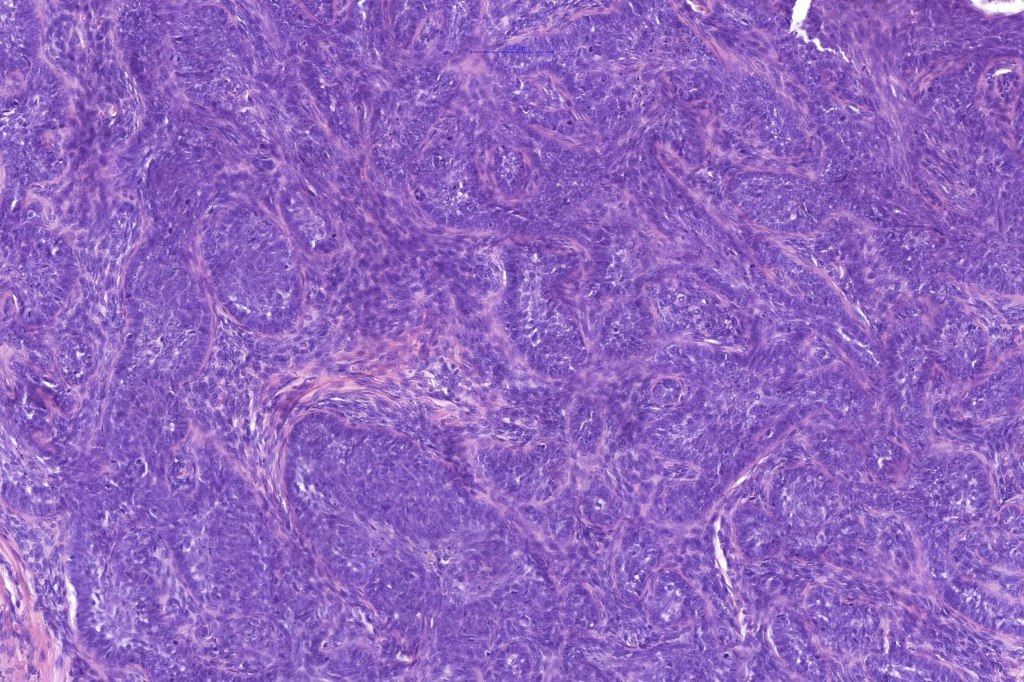

Histological features

•Biphasic tumors comprising germinative epithelial and mesenchymal components

•Sharply circumscribed nodule, sometimes with a pseudocapsule

•Uniform basaloid cells with peripheral palisading and often marked mitotic activity

•No pleomorphism

•Absence of retraction artifact and mucin deposition